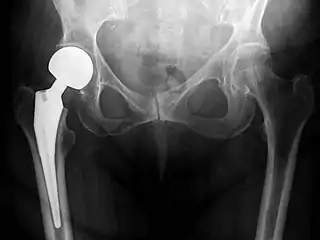

Post-operative projectional radiography is routinely performed to ensure proper configuration of hip prostheses.

X-ray of the hips, with a right-sided hemiarthroplasty.